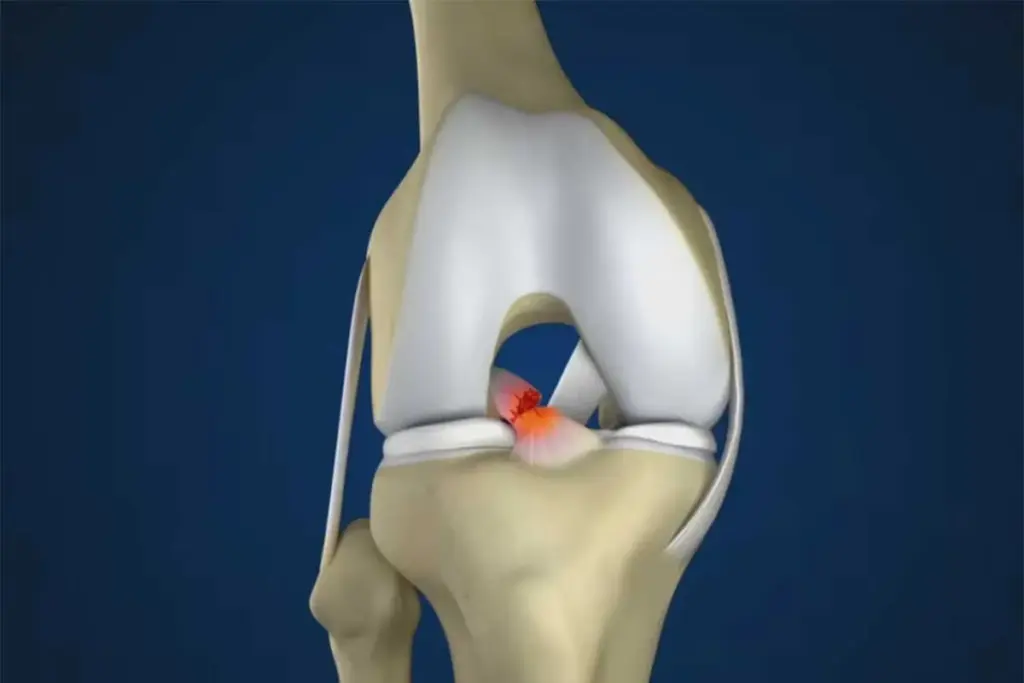

Understanding ACL Injuries and Reconstruction Needs

ACL injuries are common, affecting many people. This includes athletes and those who play sports for fun. The ACL is key for knee stability. Injuries can really change someone’s life.

Why Surgical Reconstruction Is Often Necessary

Surgery is often needed to fix knee stability and function. Whether to have surgery depends on the injury’s severity, the patient’s age, and how active they are. For many, surgery is the best way to get a stable and working knee.